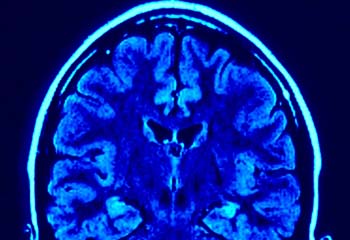

Un escáner cerebral para medir la capacidad de liderazgo

Un equipo de neurocientíficos, psicólogos y expertos en Gestión de la Universidad de Reading, en Reino Unido, están colaborando en un estudio con el que pretenden averiguar si es posible detectar la capacidad de liderazgo de los ejecutivos mediante un escáner cerebral.

Para ello, una serie de directivos de empresas se han sometido a una resonancia magnética al tiempo que completan por ordenador una serie de ejercicios sobre decisiones financieras. "Lo que se les pide es que decidan si, en función de cierta información, es mejor tomar una decisión a corto o largo plazo", añade el profesor Douglas Saddy, que también colabora en el estudio.

De este modo, mientras el ejecutivo presiona el teclado se mide su actividad cerebral y, junto con el resultado de estas pruebas y otros escáneres, se intentarán extraer algunas conclusiones.